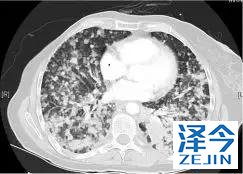

一位77岁的女性患有EPS15-NTRK1 IV期非小细胞肺癌,我们可以看到她的双肺满是病灶,并且出现了肝脏和脑转移,可以说是非常非常晚期了,

肺靶病变达到缓解,我们可以明显的看到前后的图像,病灶明显缩小了,

脑转移病变显示缩小了95%!

初始, 2018年6月 3周期 2018年8月